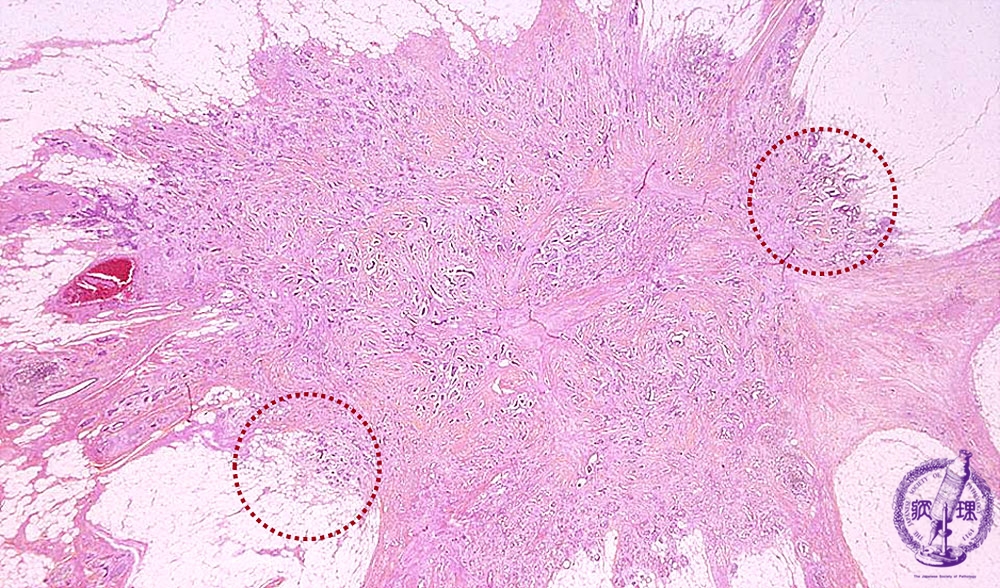

- ★(6)Invasive ductal carcinoma(Scirrhous carcinoma)

Microscopic image(HE stain, low power view):Tumor margin irregular with fluffing, representing the infiltration to adjacent adipose tissue.